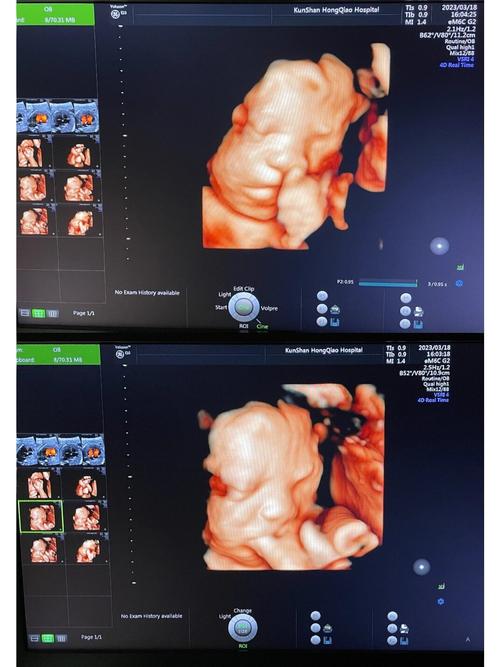

四维成像技术,通常指的是三维成像技术加上时间维度,即可以捕捉到物体在三维空间中的动态变化,在医学、安全监控等领域有着广泛的应用。